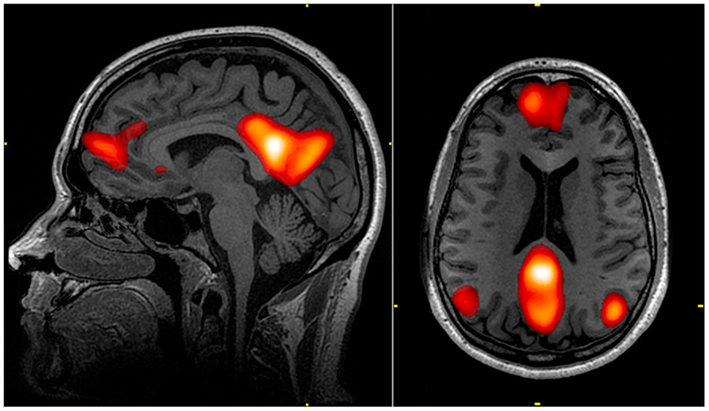

La DMN es una región del cerebro que se activa cuando no estamos concentrados en una tarea específica, es decir, cuando nuestra mente está “en reposo”. En otras palabras, esta red sería como el “piloto automático” del cerebro. Pues, se activa cuando no estamos enfocados en una tarea específica. Pero también, desempeña un papel importante en la regulación de emociones, la toma de decisiones y recuperación de recuerdos. En añadidura, es sensible a los estados emocionales y ritmo circadiano.

Por otro lado, esta red se divide en tres principales subdivisiones (Raichle, 2015):

- Corteza prefrontal ventral media: Relacionada con la recepción de información sensorial del mundo exterior y del cuerpo. La información que recibe la transmite a áreas cerebrales responsables de regular las emociones, comportamiento social y motivación. Asimismo, su actividad está influenciada por el estado emocional de la persona, disminuyendo cuando la ansiedad es alta y aumentando cuando disminuye.

- Corteza prefrontal medial dorsal: A diferencia de la anterior, esta área está más relacionada con la toma de decisiones y juicios sobre uno mismo. Por lo tanto, al realizar tareas que requieren atención y concentración se activa, mientras que la anterior se desactiva.

- Corteza cingulada posterior y precúneo medial: Por último, las siguientes regiones están involucradas en la recuperación de información previamente almacenada en la memoria. Además, muestran una fuerte conexión con el hipocampo, que desempeña un rol relevante en la memoria. Curiosamente, la actividad de esta red varía durante el día, siendo más fuerte por la noche y más débil por la mañana después de una noche de sueño.